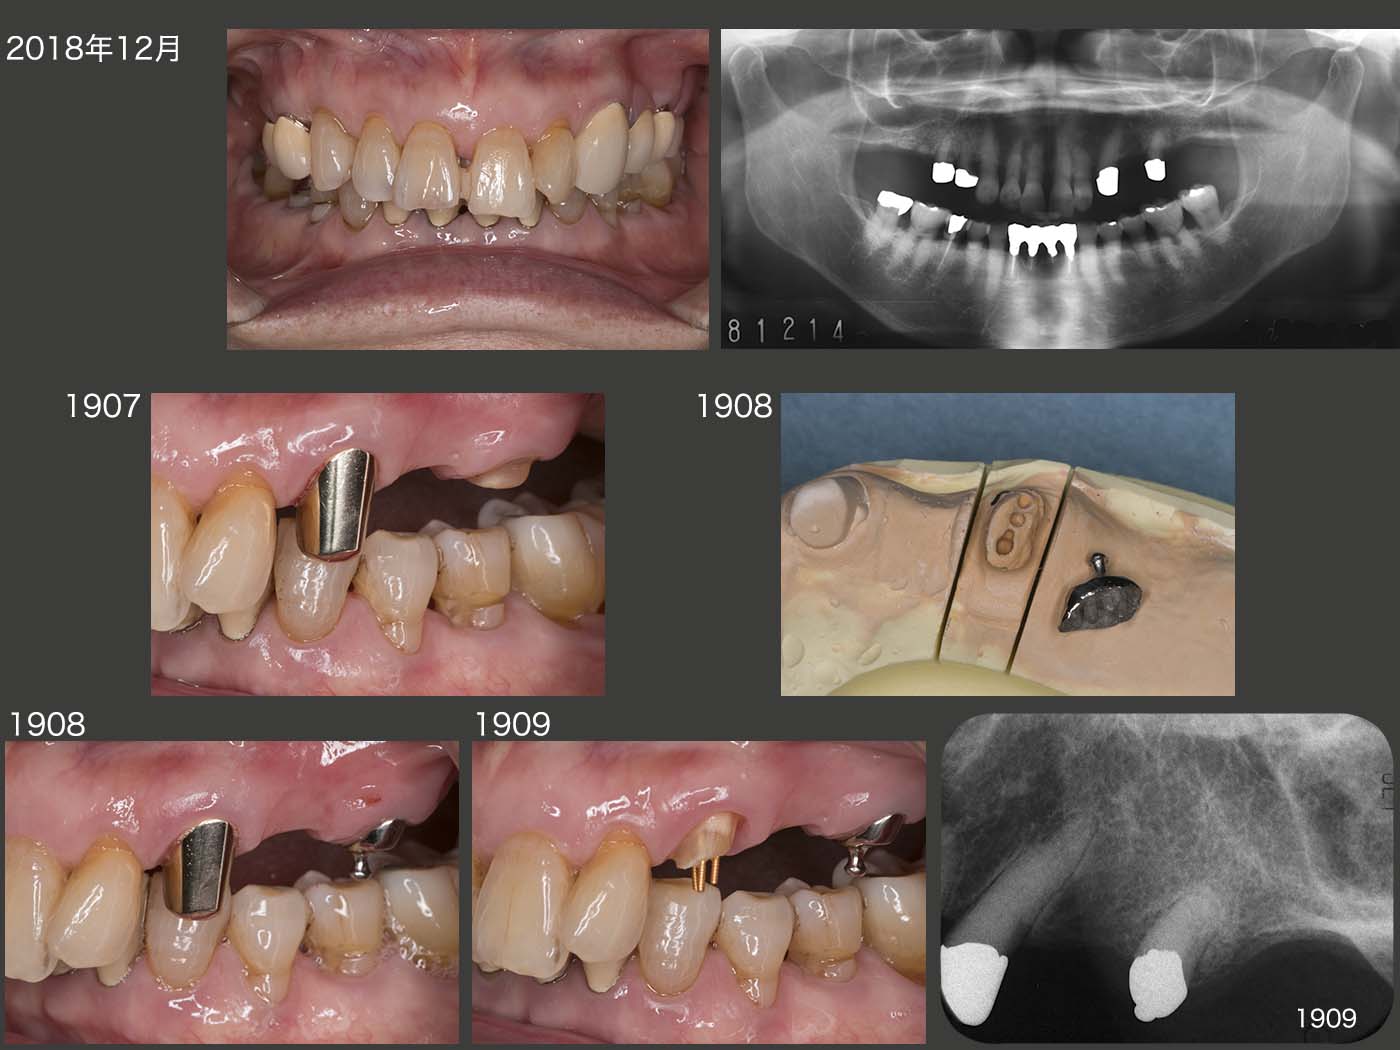

2018年12月までの5年4ヵ月間,特に問題なく経過した.しかし,19年7月,左上5の内冠が歯冠破折した.本来なら抜髄して,根管保持の補綴装置を製作するところであるが,今回は有髄のままOPAアタッチメントを装着した.(どこまで保てるか疑問ではあるが)なお,装着時に患者さんから左上3も外れていると言われたが,本当に左上3の内冠も歯冠破折していた.こちらはまだ歯肉縁上歯質が残っていたので,ピンを用いて内冠を再合着した.

2019年11月の状態.それにしても,有髄歯が2本続けて歯冠破折するとは想像していなかったとともに,有髄のままリカバリーできて本当に良かった.12年の時に心配した右上4は,両側性設計にすることで連結固定効果が強固になったことが幸いしたからか,その後小康を保っている.